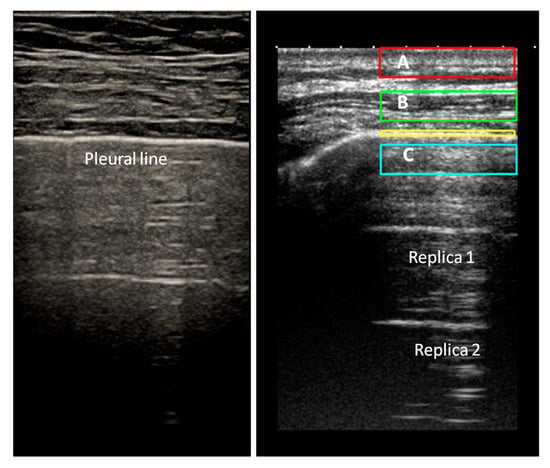

Figure 5.

(A): Acute cardiogenic pulmonary edema, histopathologic picture. (B): Idiopatic Pulmonary Fibrosis (IPF), histopathologic picture. In acute pulmonary edema the lung shows little structural changes and this is especially evident in early hydrostatic edema, when only the interlobular septa show a moderate smooth thickening. On the contrary, in IPF the lung is involved by variable amount of fibrosis and it is deeply subverted in the structure. (C) and (D): The related ultrasound pictures. In cardiogenic pulmonary edema (C) pleural line is regular and smooth (Image obtained with a commercially available machine, Esaote MyLab 25 equipped with a Convex probe), in IPF (D), pleural line is irregular and the artefacts are very heterogeneous (Image obtained with a commercially available machine, Toshiba Aplio XV, equipped with a convex probe, 3 MHz, without harmonic imaging).

Sonographic diagnosis of pulmonary edema and ARDS is well known and appreciated in Emergency Medicine and Critical Care settings. The use of lung ultrasound is less common among pulmonologists for the study of interstitial pulmonary disease [42,43]. In 2008, some criteria for ultrasound differential diagnosis between ARDS and Cardiogenic Pulmonary Edema (CPE) were proposed [35]. The differences concerned the regularity of the pleural line in CPE and the distribution of the artifacts, more regular in CPE and showing a patchy aspect with spared areas in ARDS. In 2017, these criteria were reviewed [36], paying particular attention to the morphology of the individual artifacts and hypothesizing a correlation between their appearance and the sub-pleural histology, obviously different in the two pathologic conditions. Moreover, there is no doubt that independently of the pulmonary density, the ultrasound picture of the lung in CPE is very different (Figure 5) from that of primitive and secondary pulmonary interstitial disease [36,44]. These observations support the hypothesis that the superficial histopathology of the lung responds to ultrasound through the creation of different acoustic traps in the different pathologies, which are capable of conditioning the appearance of the vertical artifact and their distribution along the pleural surface.